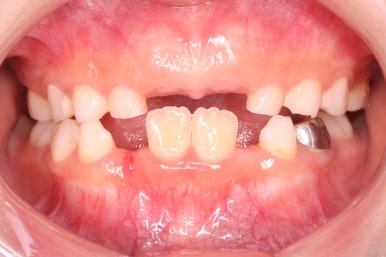

부산어린이치아교정 키다리아저씨치과에 처음 내원하셨을 당시의 입안의 모습입니다. 네 군데 모두 어금니는 보이지 않습니다.

입 안에서 문제점이 발견되지 않는 경우 일이 커지는 경우가 많은데 이번 환자분은 X-ray를 찍어봄으로써 문제를 조기에 발견하고 치료를 할 수 있었습니다.

얼굴 모습입니다.

아래턱이 크다거나 하는 턱뼈의 문제점은 보이지 않았습니다.